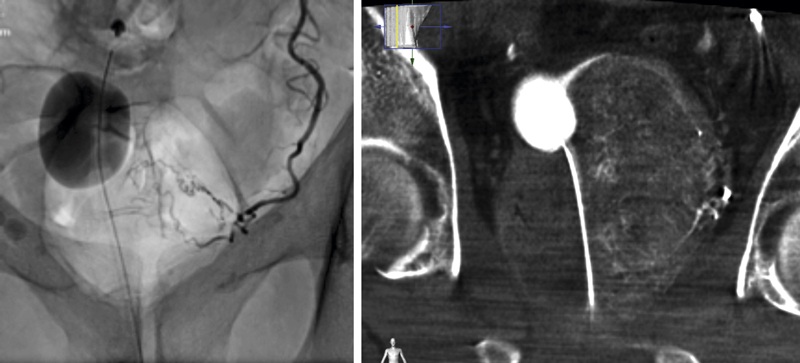

Prostataartärembolisering introducerad i Sverige

Interventionell radiologi är nu certifierad i Sverige